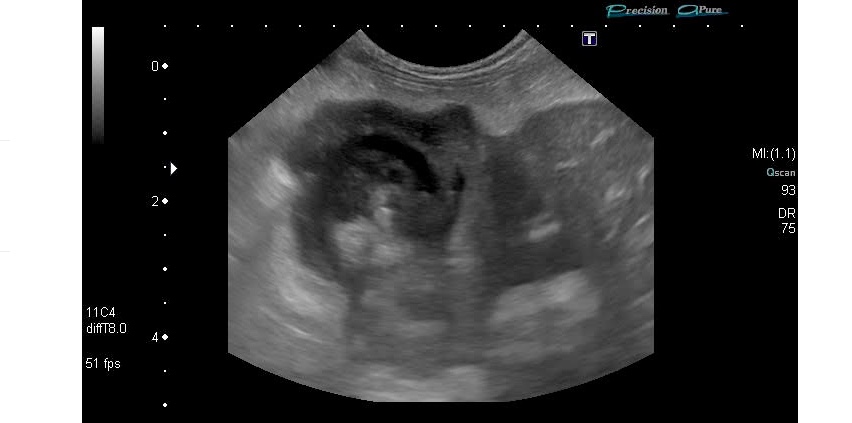

超音波検査では胆嚢内に高エコー物が認められ、胆嚢壁は肥厚していました。

また、胆嚢周囲の脂肪組織は高エコーを呈し、腹水を疑う所見があることから、胆嚢壁の破裂が起きていると考えました。

退院後、経過観察を行なって行きましたが、超音波検査で胆嚢には依然として胆嚢内の高エコー物や胆嚢の肥厚が認められました。